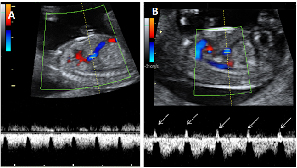

Ecografía Embarazo 2D y 3D Semana 12 - PRUEBAS DIAGNÓSTICAS

Ecografía Embarazo 4D Semana 12 - PRUEBAS DIAGNÓSTICAS